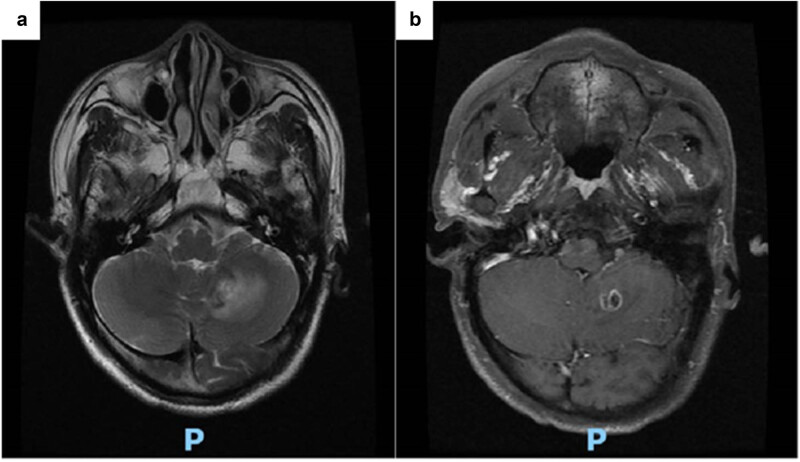

肺隐球菌病是一种由新型隐球菌或加蒂隐球菌引起的侵袭性真菌感染。它的临床表现和放射学表现通常是非特异性的,使得早期诊断具有挑战性。在这里,一个44岁的男性谁提出头晕和头痛的情况下,报告。最初的颅脑磁共振成像和胸部计算机断层扫描(平扫和增强扫描)提示肺癌伴脑转移。只有在肺肿块活检、细胞学涂片和组织病理学分析证实PC后,才确定了明确的诊断。术后给予抗真菌治疗,效果良好。本病例强调了在鉴别诊断中考虑PC的重要性,以便及时诊断和治疗,潜在地降低相关死亡率。

Pulmonary cryptococcosis (PC) is an invasive fungal infection caused by Cryptococcus neoformans or Cryptococcus gattii. Its clinical presentation and radiological findings are often non-specific, making early diagnosis challenging. Herein, the case of a 44-year-old male who presented with dizziness and headache is reported. Initial cranial magnetic resonance imaging and chest computed tomography (plain and contrast-enhanced) suggested lung cancer with brain metastasis. A definitive diagnosis was established only after a lung mass biopsy, followed by a cytological smear and histopathological analysis, confirmed PC. The patient was treated with antifungal therapy postoperatively and responded well. This case underscores the importance of considering PC in differential diagnoses to enable prompt diagnosis and treatment, potentially reducing associated mortality.